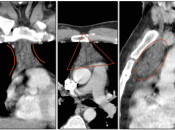

- Etiology: Hybrid Imaging

- Patient Movement

- Respiratory Motion

- Breathing Techniques